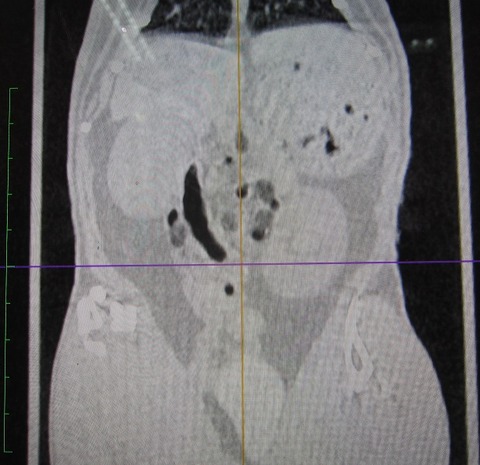

途中経過をCTで

まだまだたくさん残ってますが、👆これが👇こうなります。